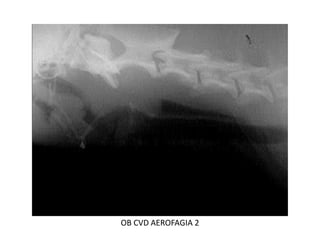

RADIOLOGIA DE CUELLO

OSCAR BENAVIDES

OB CVD columna cervical lateral

OB CVD 264Region laringea

OB CVD AEROFAGIA 2